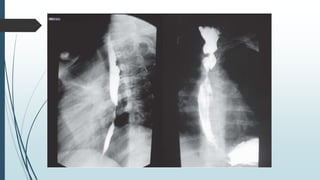

Paciente del sexo masculino, de 20 años de edad, que ingresó en agosto del

2011 al Servicio de Cirugía General por cuadro de disfagia de característica

progresiva, inicialmente a sólidos y posteriormente a líquidos, de 2 meses de

evolución, posterior a la ingesta accidental de cáusticos (soda cáustica).

Refería además astenia, anorexia y pérdida importante de peso. Se

sospecha el diagnóstico de estenosis esofágica por ingestión accidental de

cáustico. El Esofagograma (figura 1) informa retención del medio de

contraste a nivel del tercio superior esofágico, con ligera dilatación a ese

nivel, con pasaje filiforme por debajo del mismo, de 13 mm de longitud, con

irregularidad de la mucosa. La Endoscopia digestiva alta (figura 2) constató

estenosis de la luz esofágica menor a 1 cm de diámetro, con dos orificios que

podrían corresponder a procesos fistulosos, motivo por el cual se realizó una

Fibrobroncoscopía, descartándose proceso fistuloso entre el esófago y

tráquea